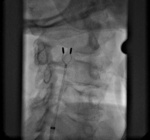

Cewnik ma kształt dwuramienny, na końcówkach jego ramion umieszczone są elektrody, między którymi płynie prąd (ryc. 2).

To on niszczy strukturę kłębka i dezaktywuje go na zawsze. W związku z rolą kłębków w organizmie, zabieg wykonywany jest wyłącznie jednostronnie.